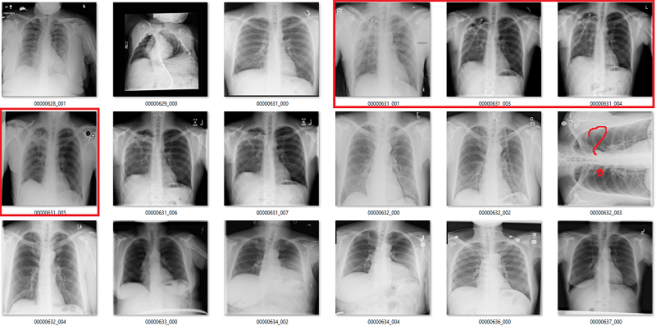

What follows is a bunch of pictures based on the labels in the dataset. In this case, they are pseudo-random. Like I said, it doesn’t have to be perfect. They are randomly chosen sequential sets of 18 images. They are not cherry-picked.

Also, I have tried to err on the side of caution, in the sense that I favour the label class when a case is equivocal.

In all the images, red = clearly wrong label. Orange = I doubt it, I wouldn’t report it, but I can’t really exclude it. Correlate clinically :p

Effusion

In this case, the blue labels mean there is significant lung disease present.

An effusion is fluid in the space around the lung. The list of causes is a mile long, but the two main groups are effusions caused by pleural disease, and those caused by lung disease.

It is not clear to me what it means to identify effusions that exist with significant lung disease. In many of these cases, it is not even really possible to visually identify the effusion, we just know that an effusion must be present so we describe it. See the last three images in the picture above for a good example of this. The main pathology in those cases is consolidation, in my opinion.

I can see value in identifying small, isolated pleural effusions. There are about a half dozen examples of these above, including the first and third images. There isn’t any lung disease to suggest the cause of effusion, which makes the effusion itself significant.

I could also see the benefit in identifying large effusions that might need intervention (like draining them with a needle). The 10th image is an example of this.

So it isn’t really clear to me what this label means. Without a guiding philosophy based in clinical practice, it isn’t very useful.